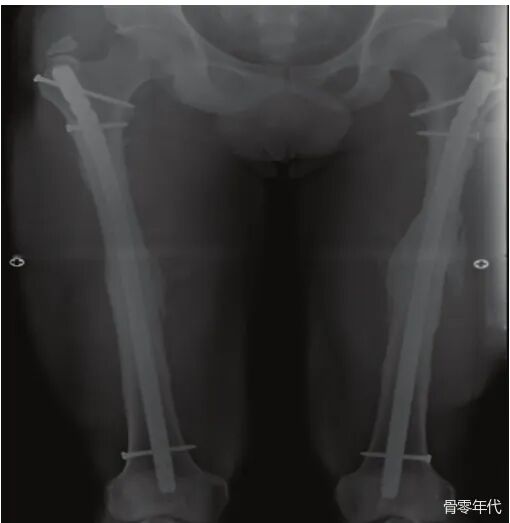

影像学表现